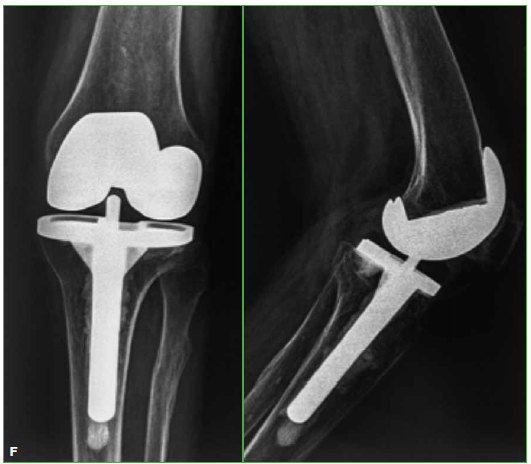

Acceso mediante suscripción PDF Acceso mediante suscripción PDF_EN (English) Acceso mediante suscripción HTML Acceso mediante suscripción Figura 1 (a-c) Acceso mediante suscripción Figura 1 (d-e) Acceso mediante suscripción Figura 1 (f) Acceso mediante suscripción Tabla 1 Acceso mediante suscripción Tabla 2 Acceso mediante suscripción Tabla 3 Acceso mediante suscripción Tabla 4